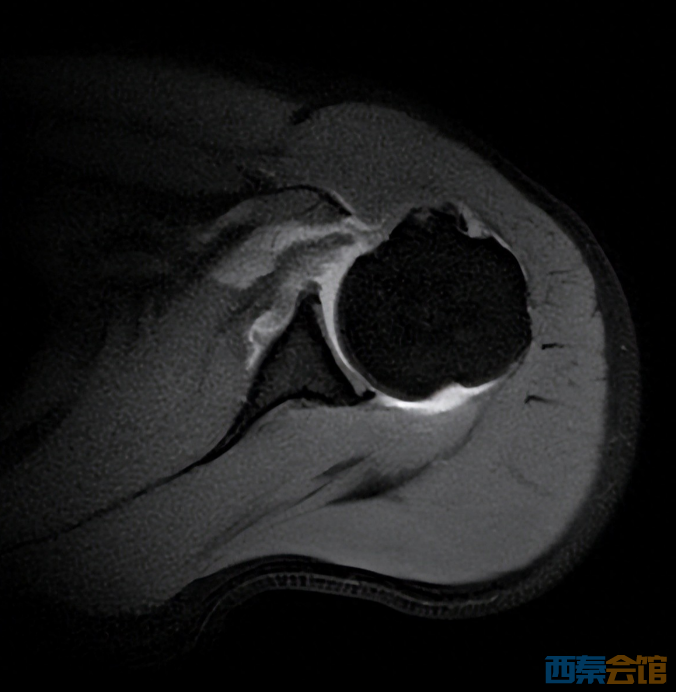

张华主任经过细致查体,怀疑这是肩胛下肌损伤。进一步的磁共振检查印证了判断,李先生肩胛下肌的止点位置撕裂了。“掰手腕时瞬间的力量不平衡,就像猛拉一根绷紧的绳子,很容易导致肩胛下肌急性撕裂。”张主任解释,李先生的这种损伤若不及时修补,肌肉会慢慢萎缩,不仅影响肩关节力量,还可能导致长期功能障碍。

为了帮李先生重新找回肩膀的“力量感”,张主任团队为他实施了关节镜下肩胛下肌撕裂修补术。手术采用微创方式,仅在肩部开几个不到1厘米的小孔,通过高清关节镜精准定位撕裂部位,再用带线锚钉,像缝衣服一样,将撕裂的肌腱牢牢缝合回原本的解剖位置。术后第二天,李先生的肩痛就明显减轻,终于能安心睡觉了。